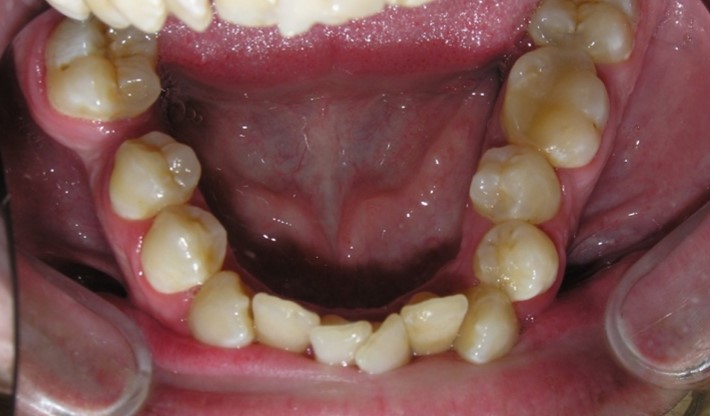

Pic.26. Crowding of the front teeth of the upper and lower jaws.